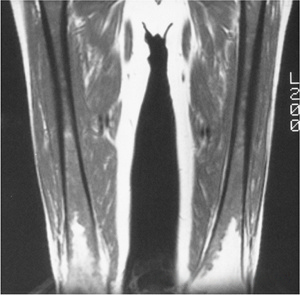

ffbc877f785f656b01216fb6a85c3f13.png

图-5髋关节缺血性坏死。T1像显示缺血性坏死,左侧更为严重。

816fffc5d8097e533c37f9acac40b5e5.png

图-6骨梗死。双膝站立位X光片显示双膝典型骨梗死的蛇行状边缘钙化。T1WI显示了梗死区和软骨下缺血性坏死。